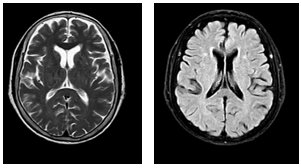

-         Cắt lớp vi tính ngực (Bệnh viện Bạch Mai): Phổi trái: Phân thùy S3 có khối tỷ trọng tổ chức kích thước 24x15mm, ngấm thuốc sau tiêm bờ không đều xâm lấn vào màng phổi trung thất, động mạch, tĩnh mạch phổi trái gây huyết khối bán phần.Xẹp thụ động thùy dưới. Màng phổi trái: có nốt ngấm thuốc đường kính 8mm. Dịch khoang màng phổi trái dày 60mm gây xẹp thụ động thùy dưới. Hạch trung thất nhóm V, nhóm II, IV bên phải và carina lớn nhất kích thước 23x12mm. Hình ảnh tổn thương tiêu xương đòn trái.

Hình 1: Hình ảnh cắt lớp vi tính ngực lúc mới nhập viện: Khối tổn thương thùy trên phổi trái, tỷ trọng tổ chức, bờ không đều, ngấm thuốc không đồng nhất, xâm lấn màng phổi trung thất (mũi tên màu đỏ). Tràn dịch màng phổi trái lượng nhiều gây xẹp phổi thụ động thùy dưới (mũi tên màu vàng).